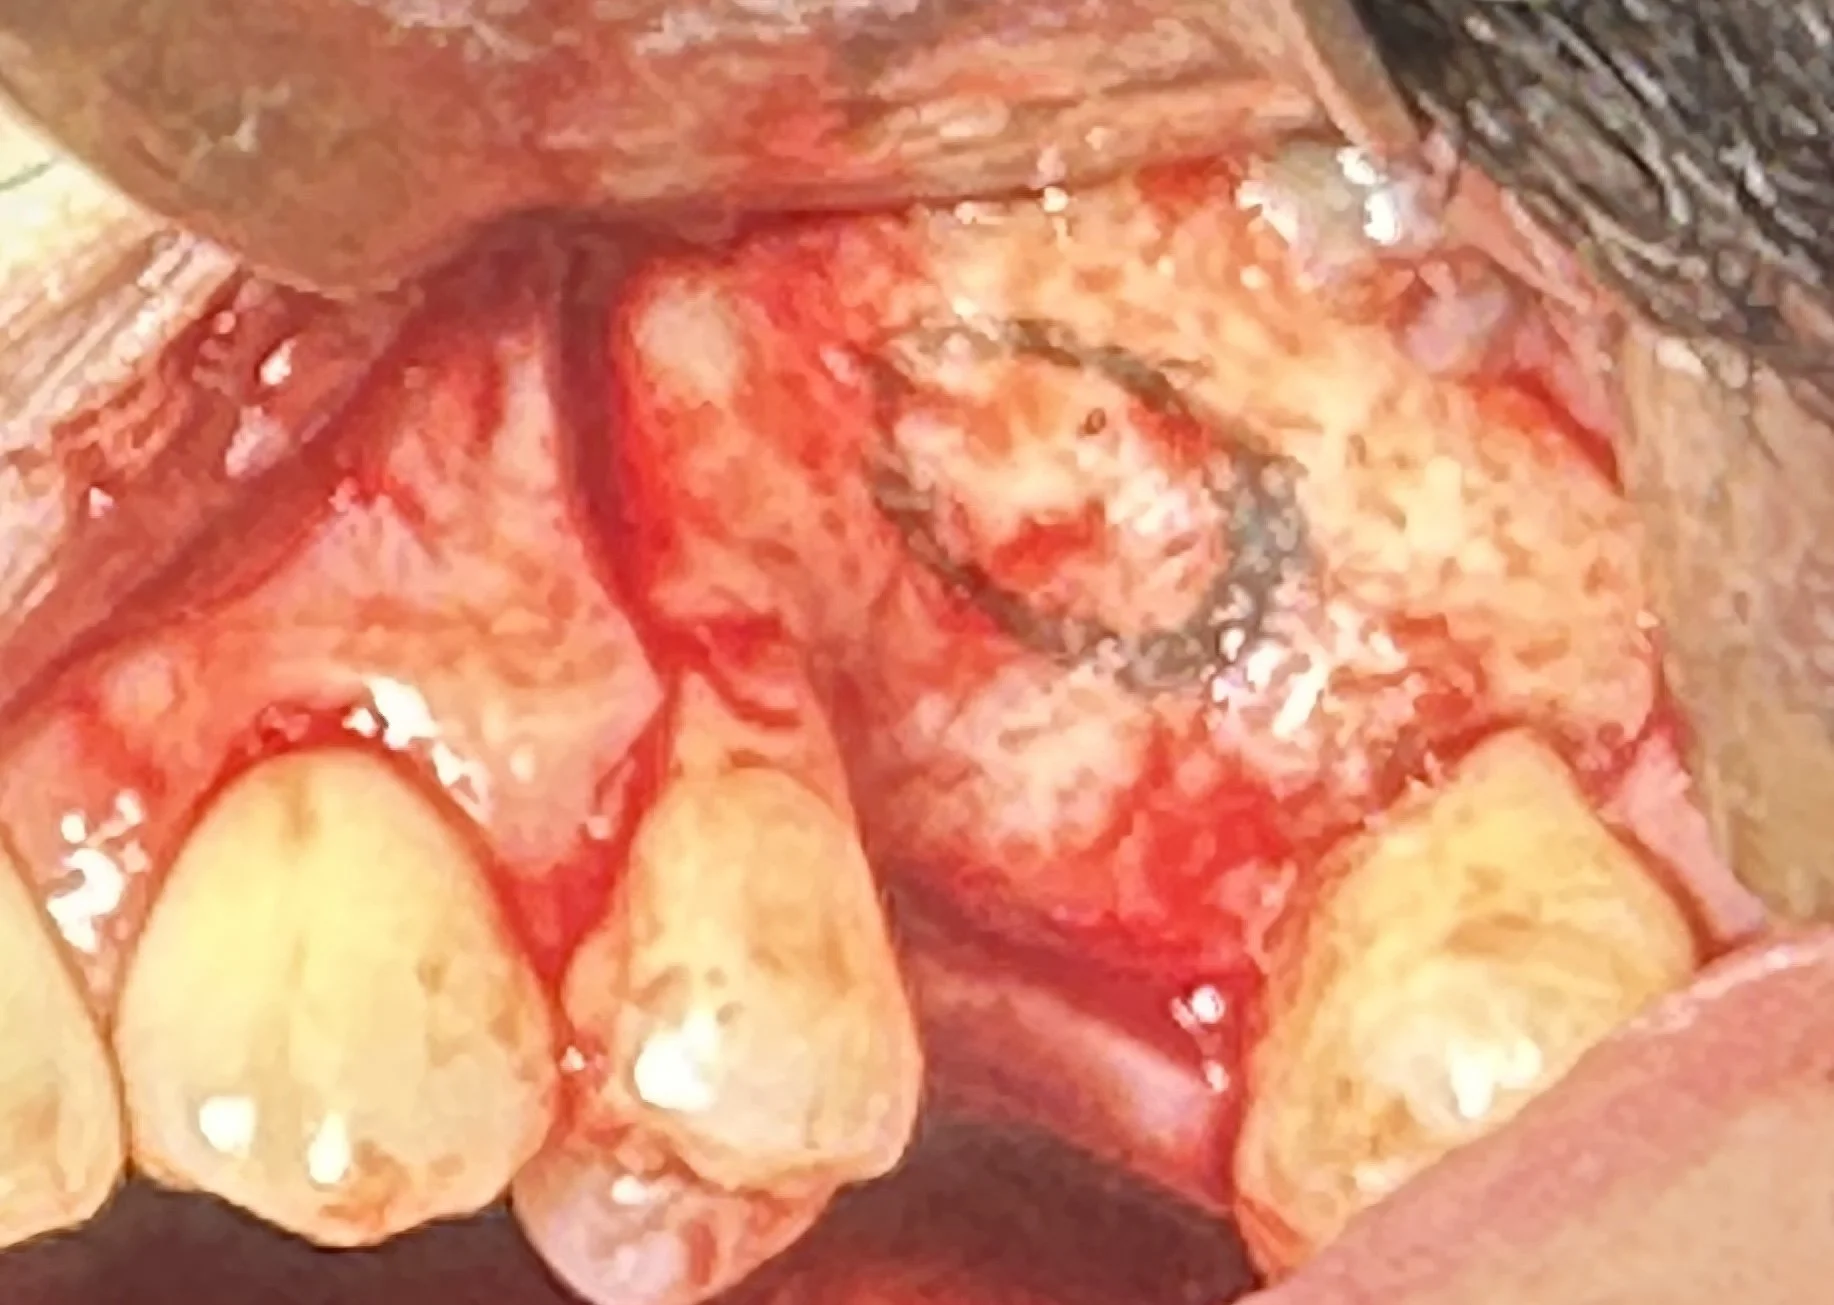

This case illustrates a lateral window sinus lift performed in the upper left molar region (tooth #14).

A small lateral window was created to access the maxillary sinus.

The Schneiderian Membrane lining the sinus cavity was carefully elevated to create space for graft material.

Bone grafting was performed to increase the vertical height and regenerate sufficient volume for future implant placement.